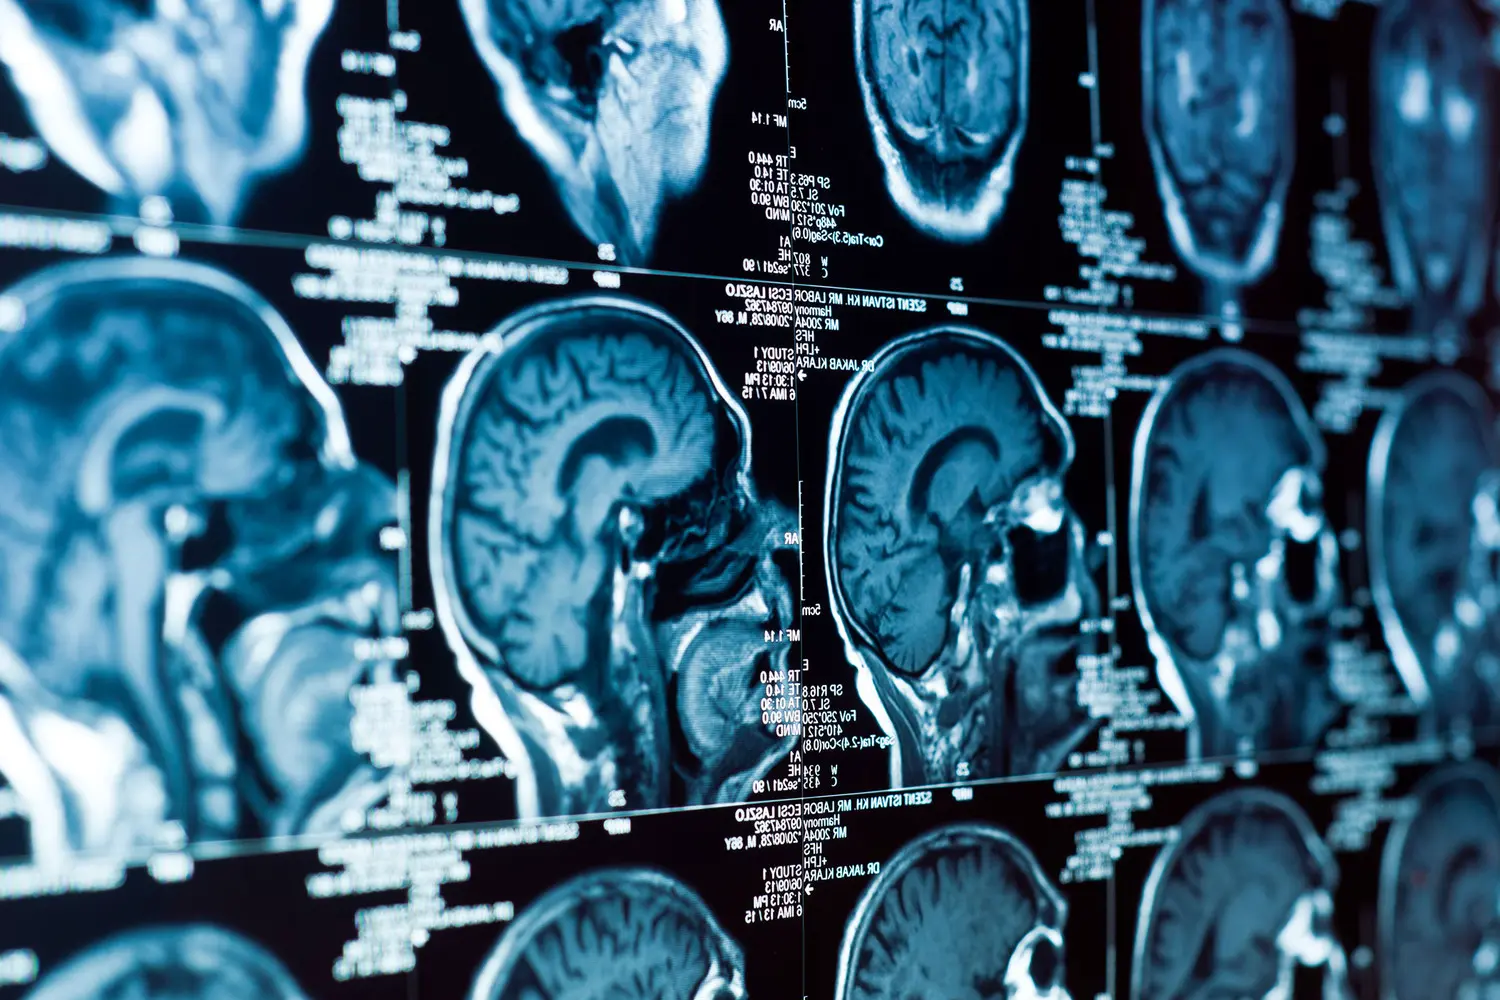

Ученые из центра Sanford Burnham Prebys определили, что особая форма ДНК – кольцевые внехромосомные элементы (вкДНК) – играет ключевую роль в рецидивах нейробластомы, агрессивного рака мозга у детей.